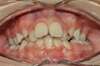

Chevauchement sévère. Traitement multibague sans extraction.

Avant

Après